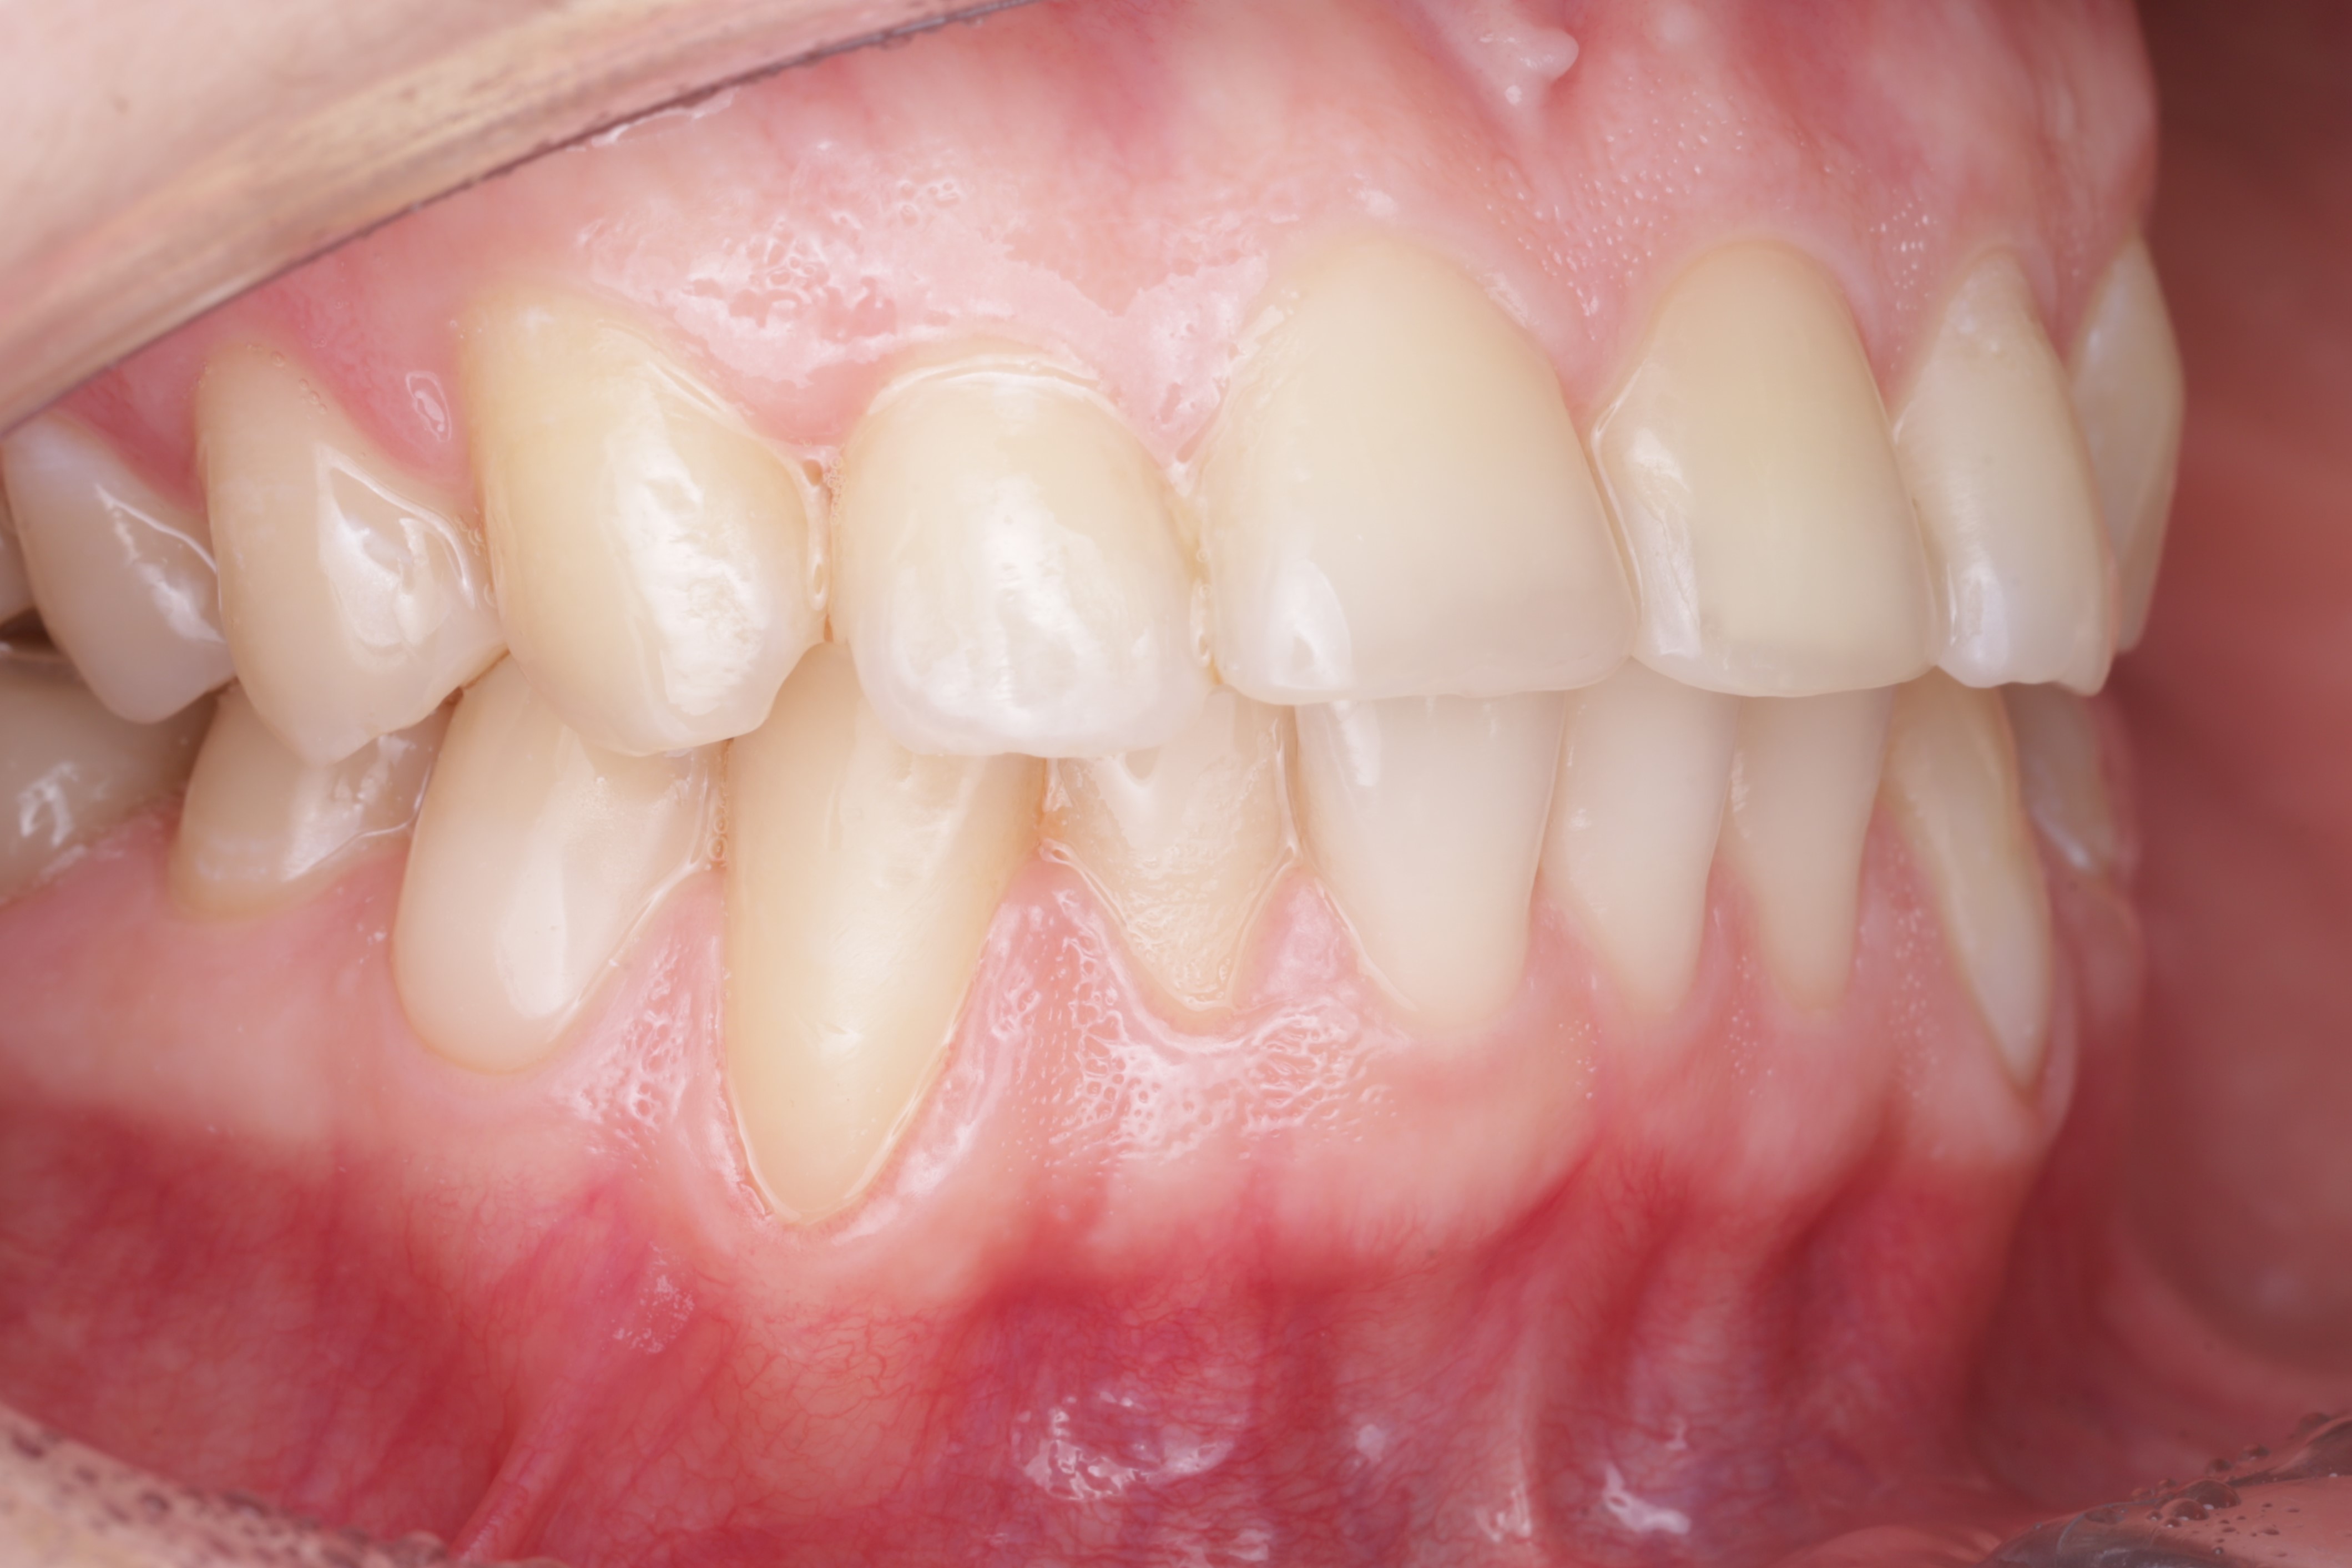

Операция была выполнена туннельной техникой с получением десневого трансплантата с нёба

Спустя два месяца ортодонт зафиксировал брекеты. Мы видим полное закрытие рецессий и увеличение толщины десны. Это делает ортодонтическое лечение безопасным, а вероятность возникновения рецессий десны в дальнейшем — минимальной или практически невозможной